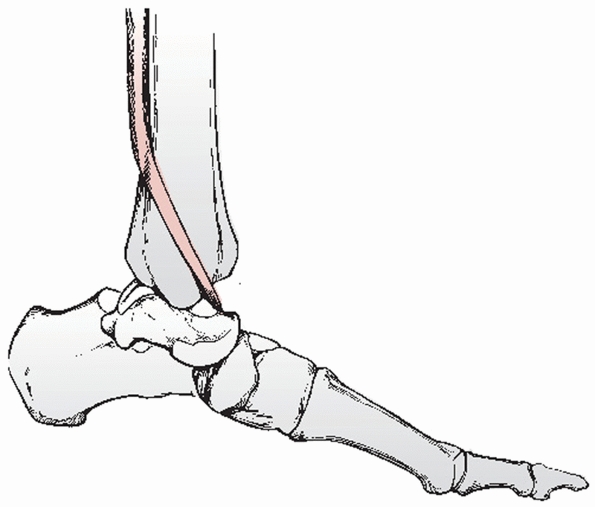

deltoid ligament and flexor hallucis longus tendon. The body of the

talus then comes to lie in the interval between the posterior aspect of

the medial malleolus and the anterior aspect of the tendo Achillis. It

mechanism, lying anterior to and being protected by the flexor hallucis

longus tendon.

occur. Frequently, however, even when the talus is dislocated

posteromedially, relative protection of the neurovascular bundle is

afforded by the flexor hallucis longus tendon such that the posterior

tibial nerve and vessel are usually intact.23